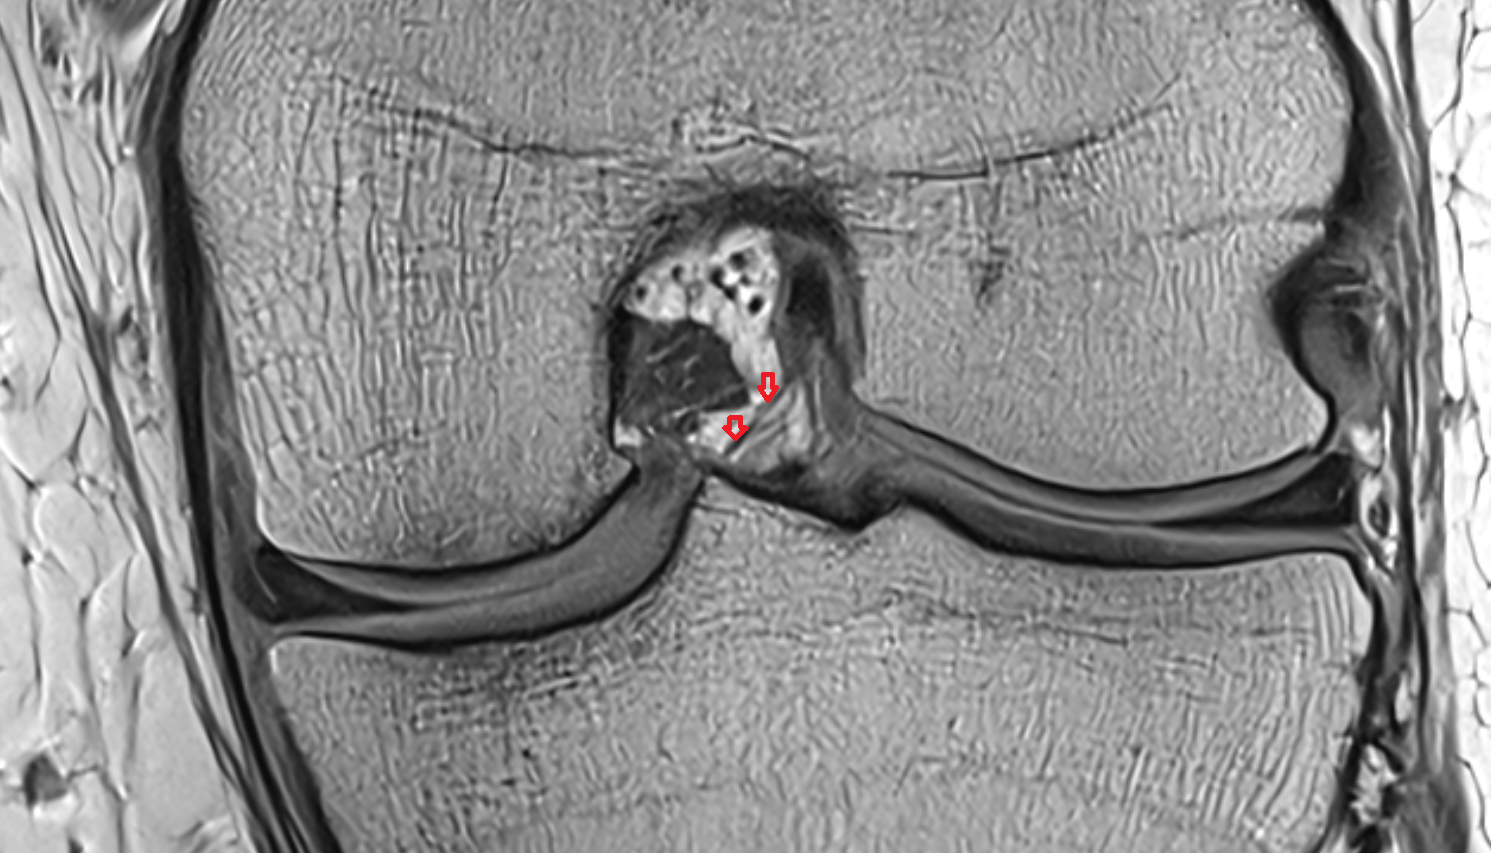

- Knee Joint